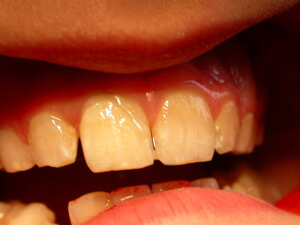

Aesthetic problems

Αισθητικά προβλήματα – εκτός από τα ορθοδοντικά – προκύπτουν και από χρωστικές που επικάθονται στα δόντια. Η χρωστική αυτή πολύ συχνά είναι μαύρη (μελανή χρωστική) και οφείλεται στα λεγόμενα χρωμογόνα μικρόβια. Επίσης, όχι και πολύ σπάνια, υπάρχουν αισθητικά προβλήματα από μη τέλειο σχηματισμό της αδαμαντίνης, πριν ακόμη ανατείλουν τα δόντια (Υπενασβεστίωση τομέων-γομφίων, ατελής αδαμαντινογένεση κλπ).